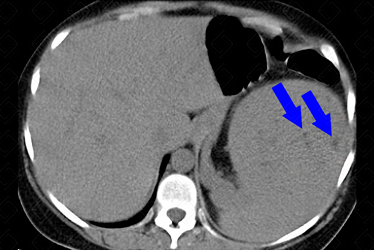

Descrição das figuras: Rins tópicos, de volume aumentado, às custas de múltiplas formações nodulares, algumas espontaneamente densas e outras com densidade de gordura, distribuídas difusamente pelo parênquima renal, bilateralmente, devendo representar cistos (setas amarelas). Destaca-se formação nodular heterogênea, com densidade predominante de gordura, no polo superior do rim direito, medindo 8,3 x 7,6 cm, compatível com angiomiolipoma (seta vermelha) Moderada esplenomegalia heterogênea, medindo 15,3 cm, às custas de pequenas formações hipodensas, devendo representar hamartomas (setas azuis). Considerar, dentre as hipóteses diagnósticas, esclerose tuberosa como a mais provável para as alterações descritas acima.

• Hepáticas e esplênicas: Presença de hamartomas são comuns nestes dois órgãos. Nestes casos, eles costumam ser múltiplos;